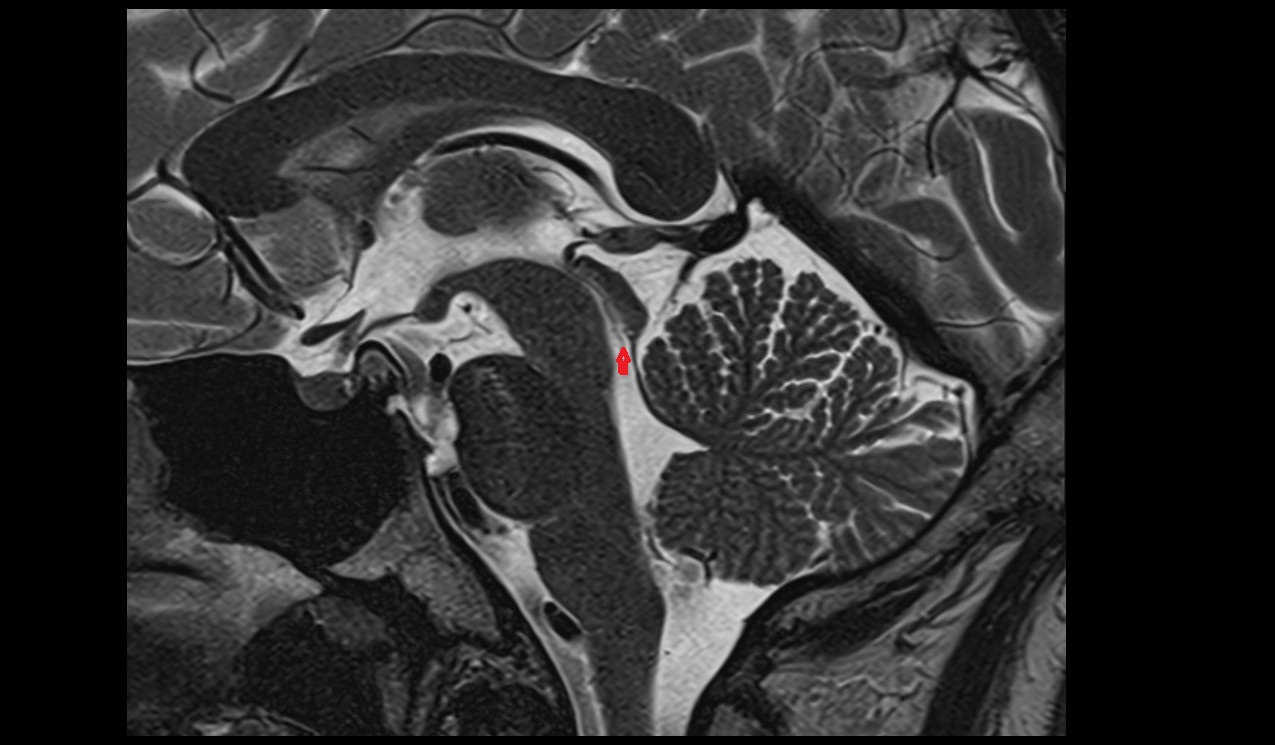

- Pituitary stalk

- Pituitary gland

- Anterior lobe of pituitary gland

- Posterior lobe pituitary gland